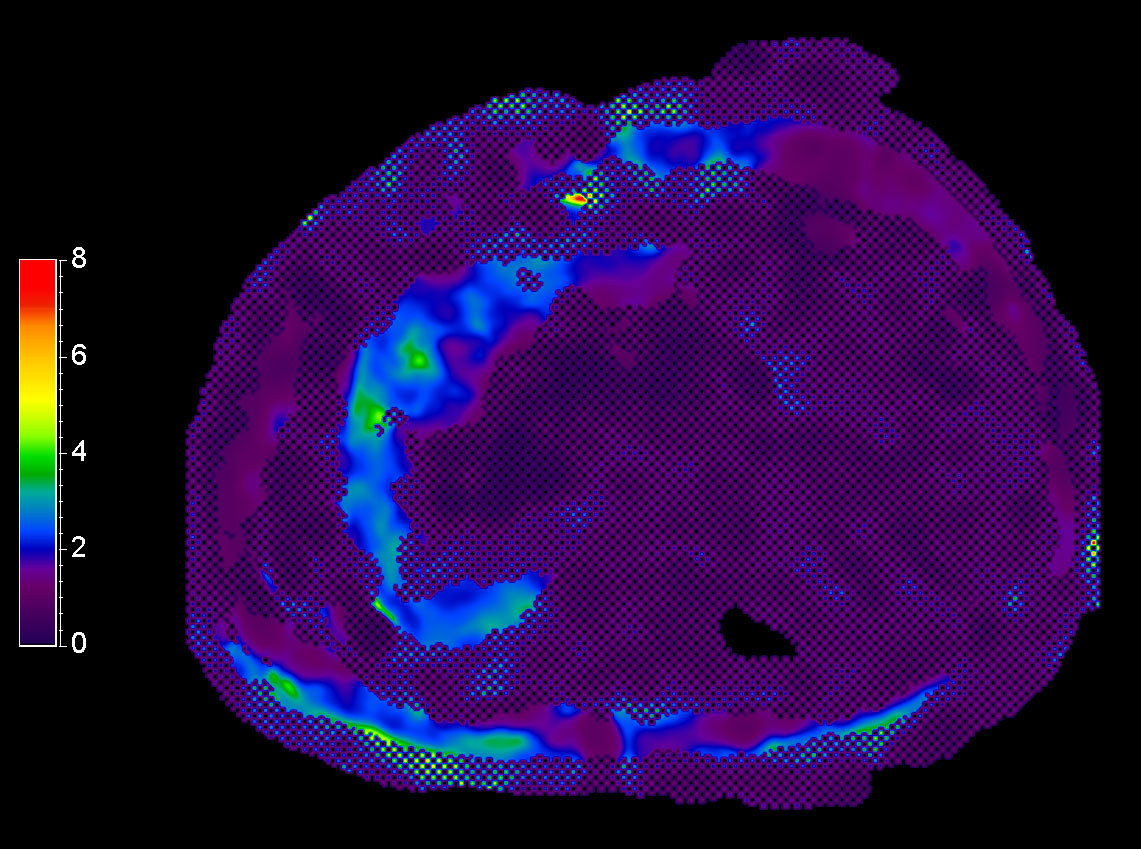

MR Elastography (stiffness map) SE-EPI, 13 sec BH/4 slices

MR Elastography (stiffness map) SE-EPI, 14 sec BH/8 slices